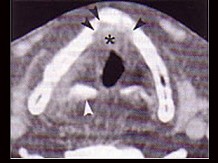

4.下面是一頸部CT圖,其中結構標志不正確的是  (    )

正確答案:D